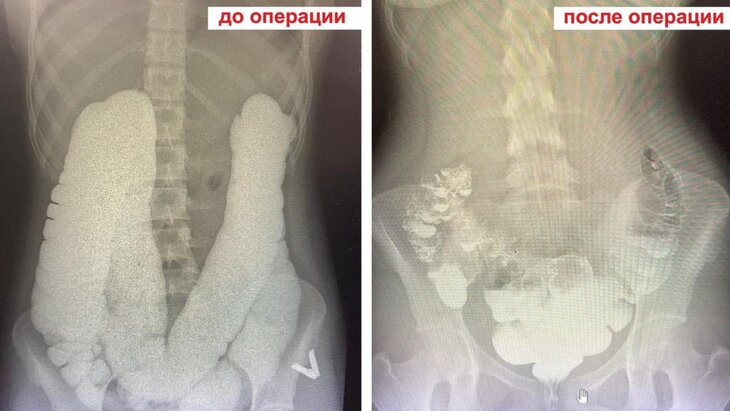

Врачи Раменской больницы спасли 17-летнюю пациентку с редким заболеванием – синдромом Пайра, сообщает телеканал "360" со ссылкой на подмосковный Минздрав.

В ходе обследования выяснилось, что у пациентки врожденная аномалия толстой кишки, из-за чего возникает чрезмерный перегиб около селезеночной связки. Это нарушило проходимость кишечника и вызвало хроническую анемию.

Заведующий детским хирургическим отделением больницы Владимир Хабалов рассказал, что медики провели малоинвазивную операцию. Через 3 прокола они сделали резекцию связочного аппарата кишечника. По его словам, техническая сложность вмешательства заключалась в восстановлении конфигурации кишки.

Операция, в рамках которой также удалили пупочную грыжу, длилась около часа. На следующий день самочувствие пациентки улучшилось. Врачи наблюдали за ней 5 дней, тогда же она проходила физиотерапию. В настоящее время девушка выписана из больницы.